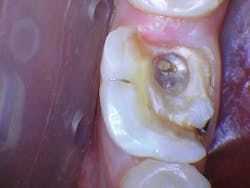

The patient presented with tooth No.19 ML with a history of endodontic treatment fractured to the level of the alveolus (figures 6-8). The patient had an inadequate clinical crown to restore. The options were either to extract the tooth and place an implant, or complete a crown lengthening and then restore. The clinical objective of crown lengthening was to establish biologic width and expose enough tooth structure coronal to the bone for a proper restoration. The patient opted for crown lengthening, and the procedure was completed in about 50 minutes.

Figure 6: Pre-op

Figure 7: Pre-op

Figure 8: Pre-op